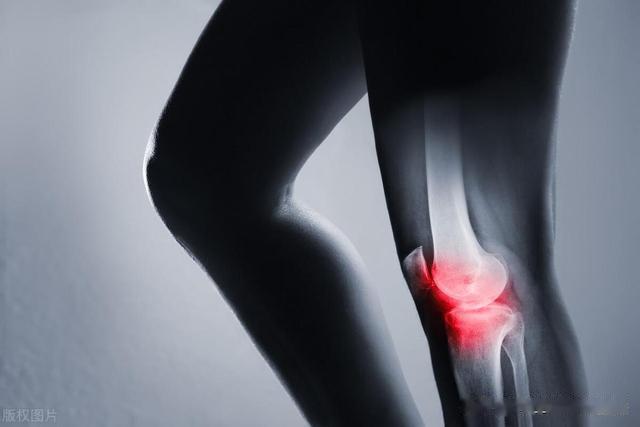

一、髌骨软化症的定义髌骨软化症,又称为髌骨软骨炎、髌骨软骨软化症,是一种以膝关节疼痛为主要临床症状的多病因造成的疾病。

其主要病理变化是软骨的退行性改变,包括软骨肿胀、碎裂、脱落,最后股骨髁的对应部位也发生同样病变,发展为髌股关节骨性关节炎。